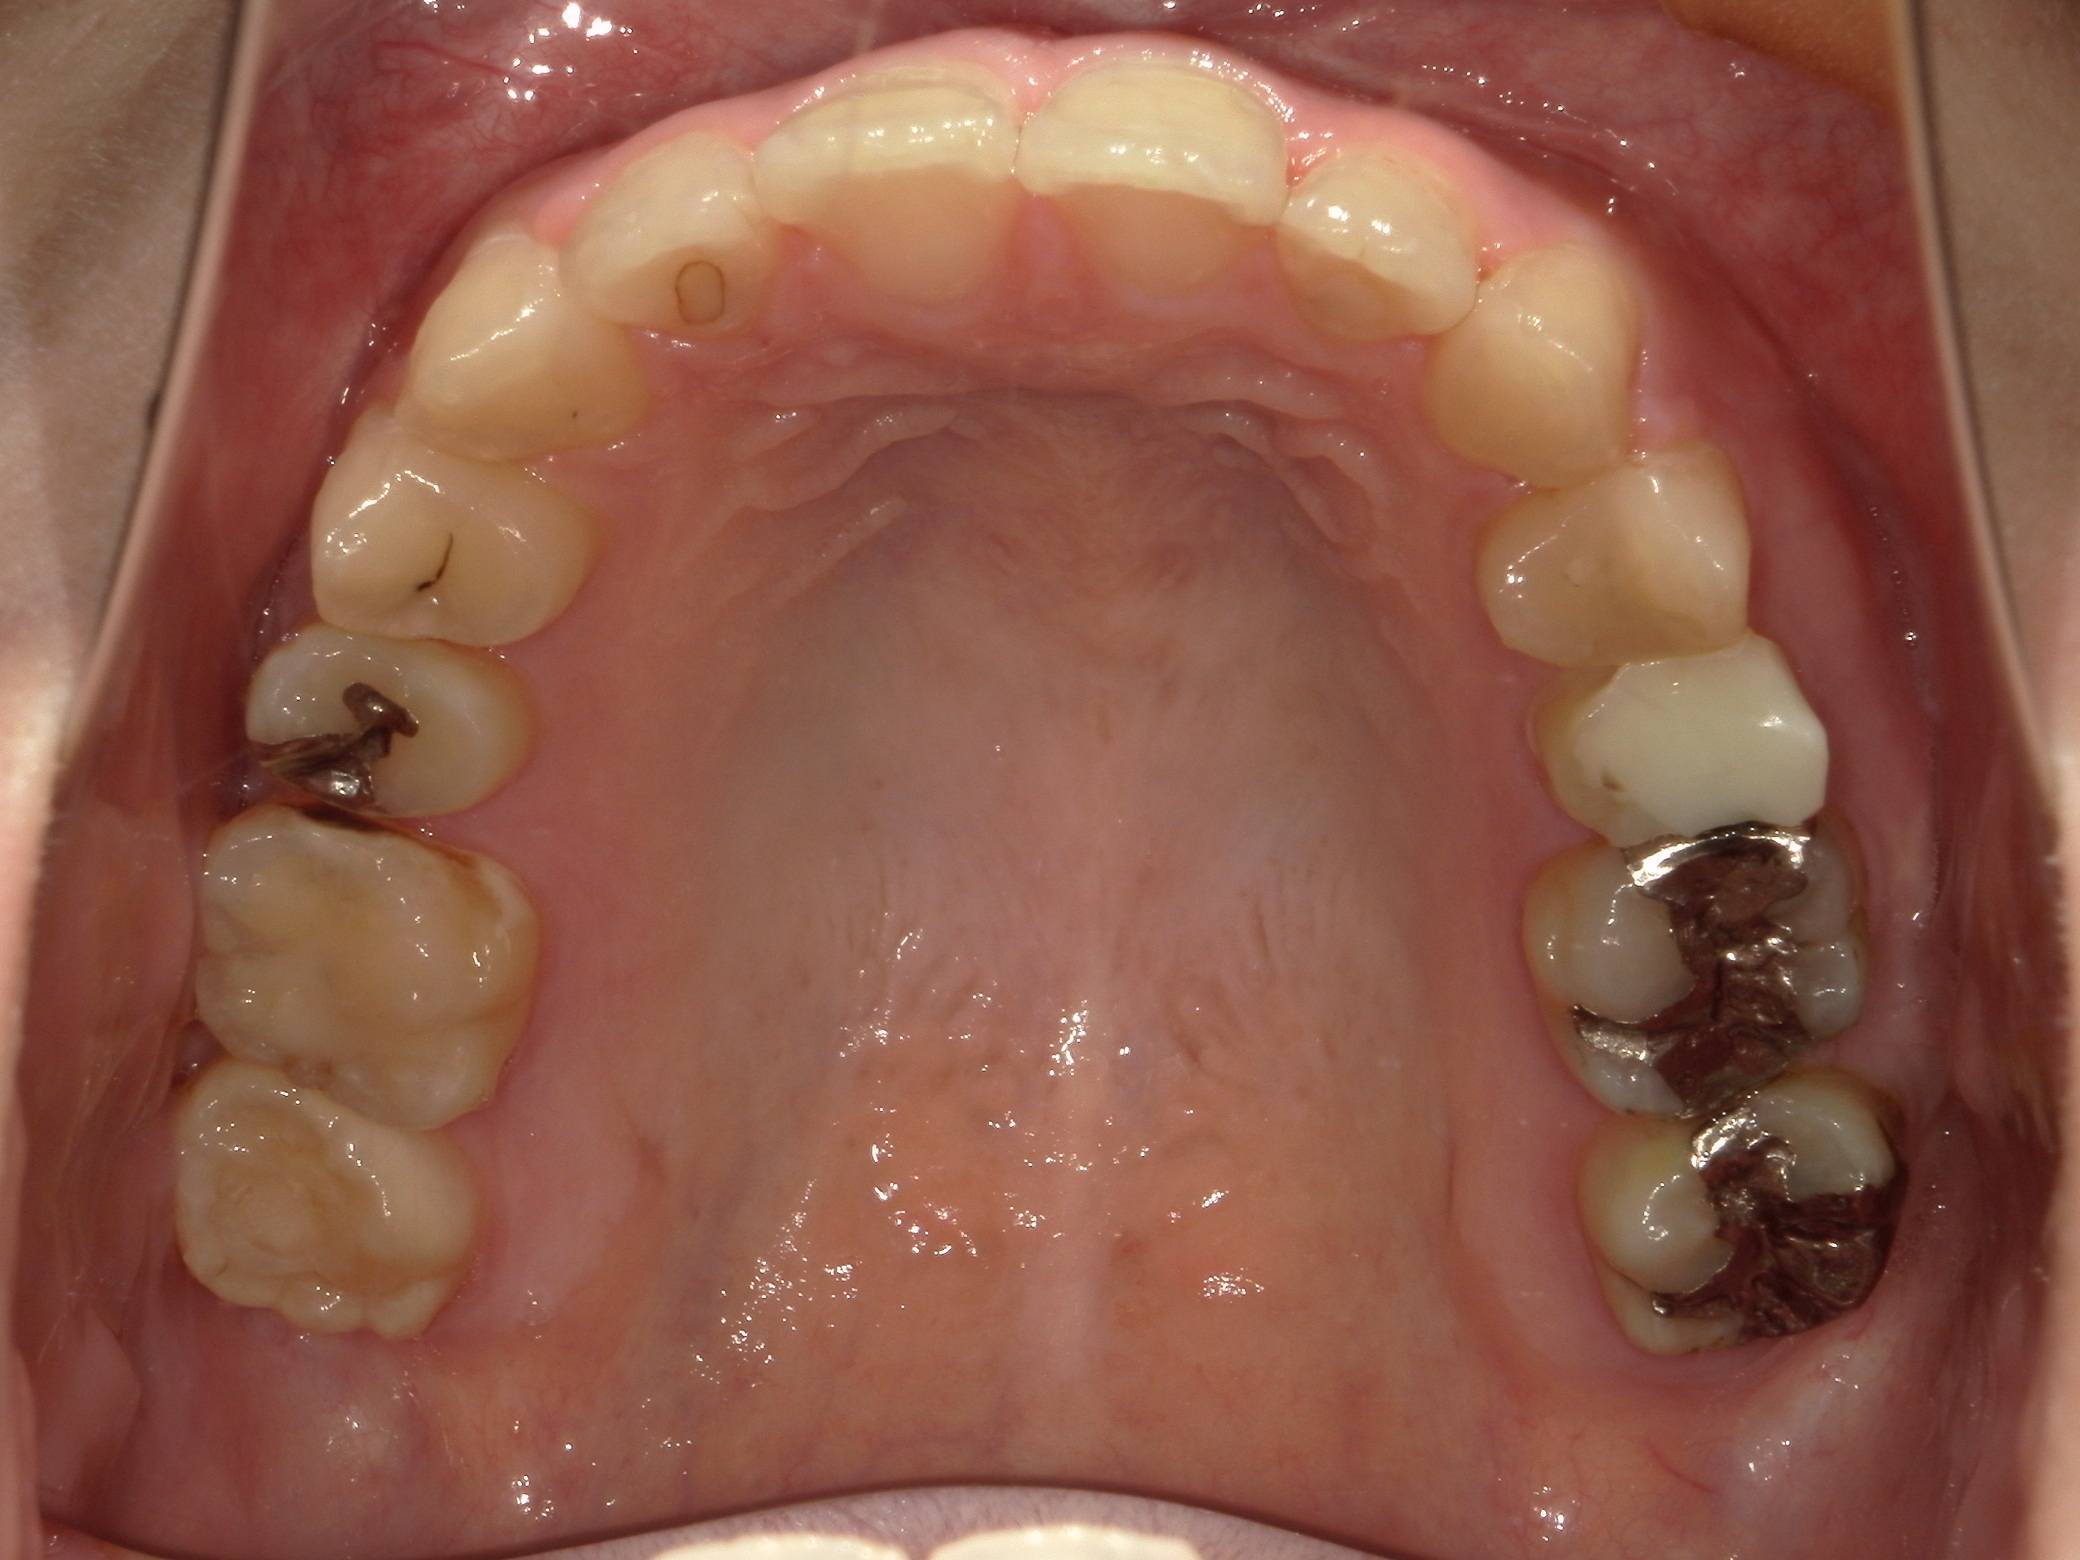

口内下

治療前

治療後